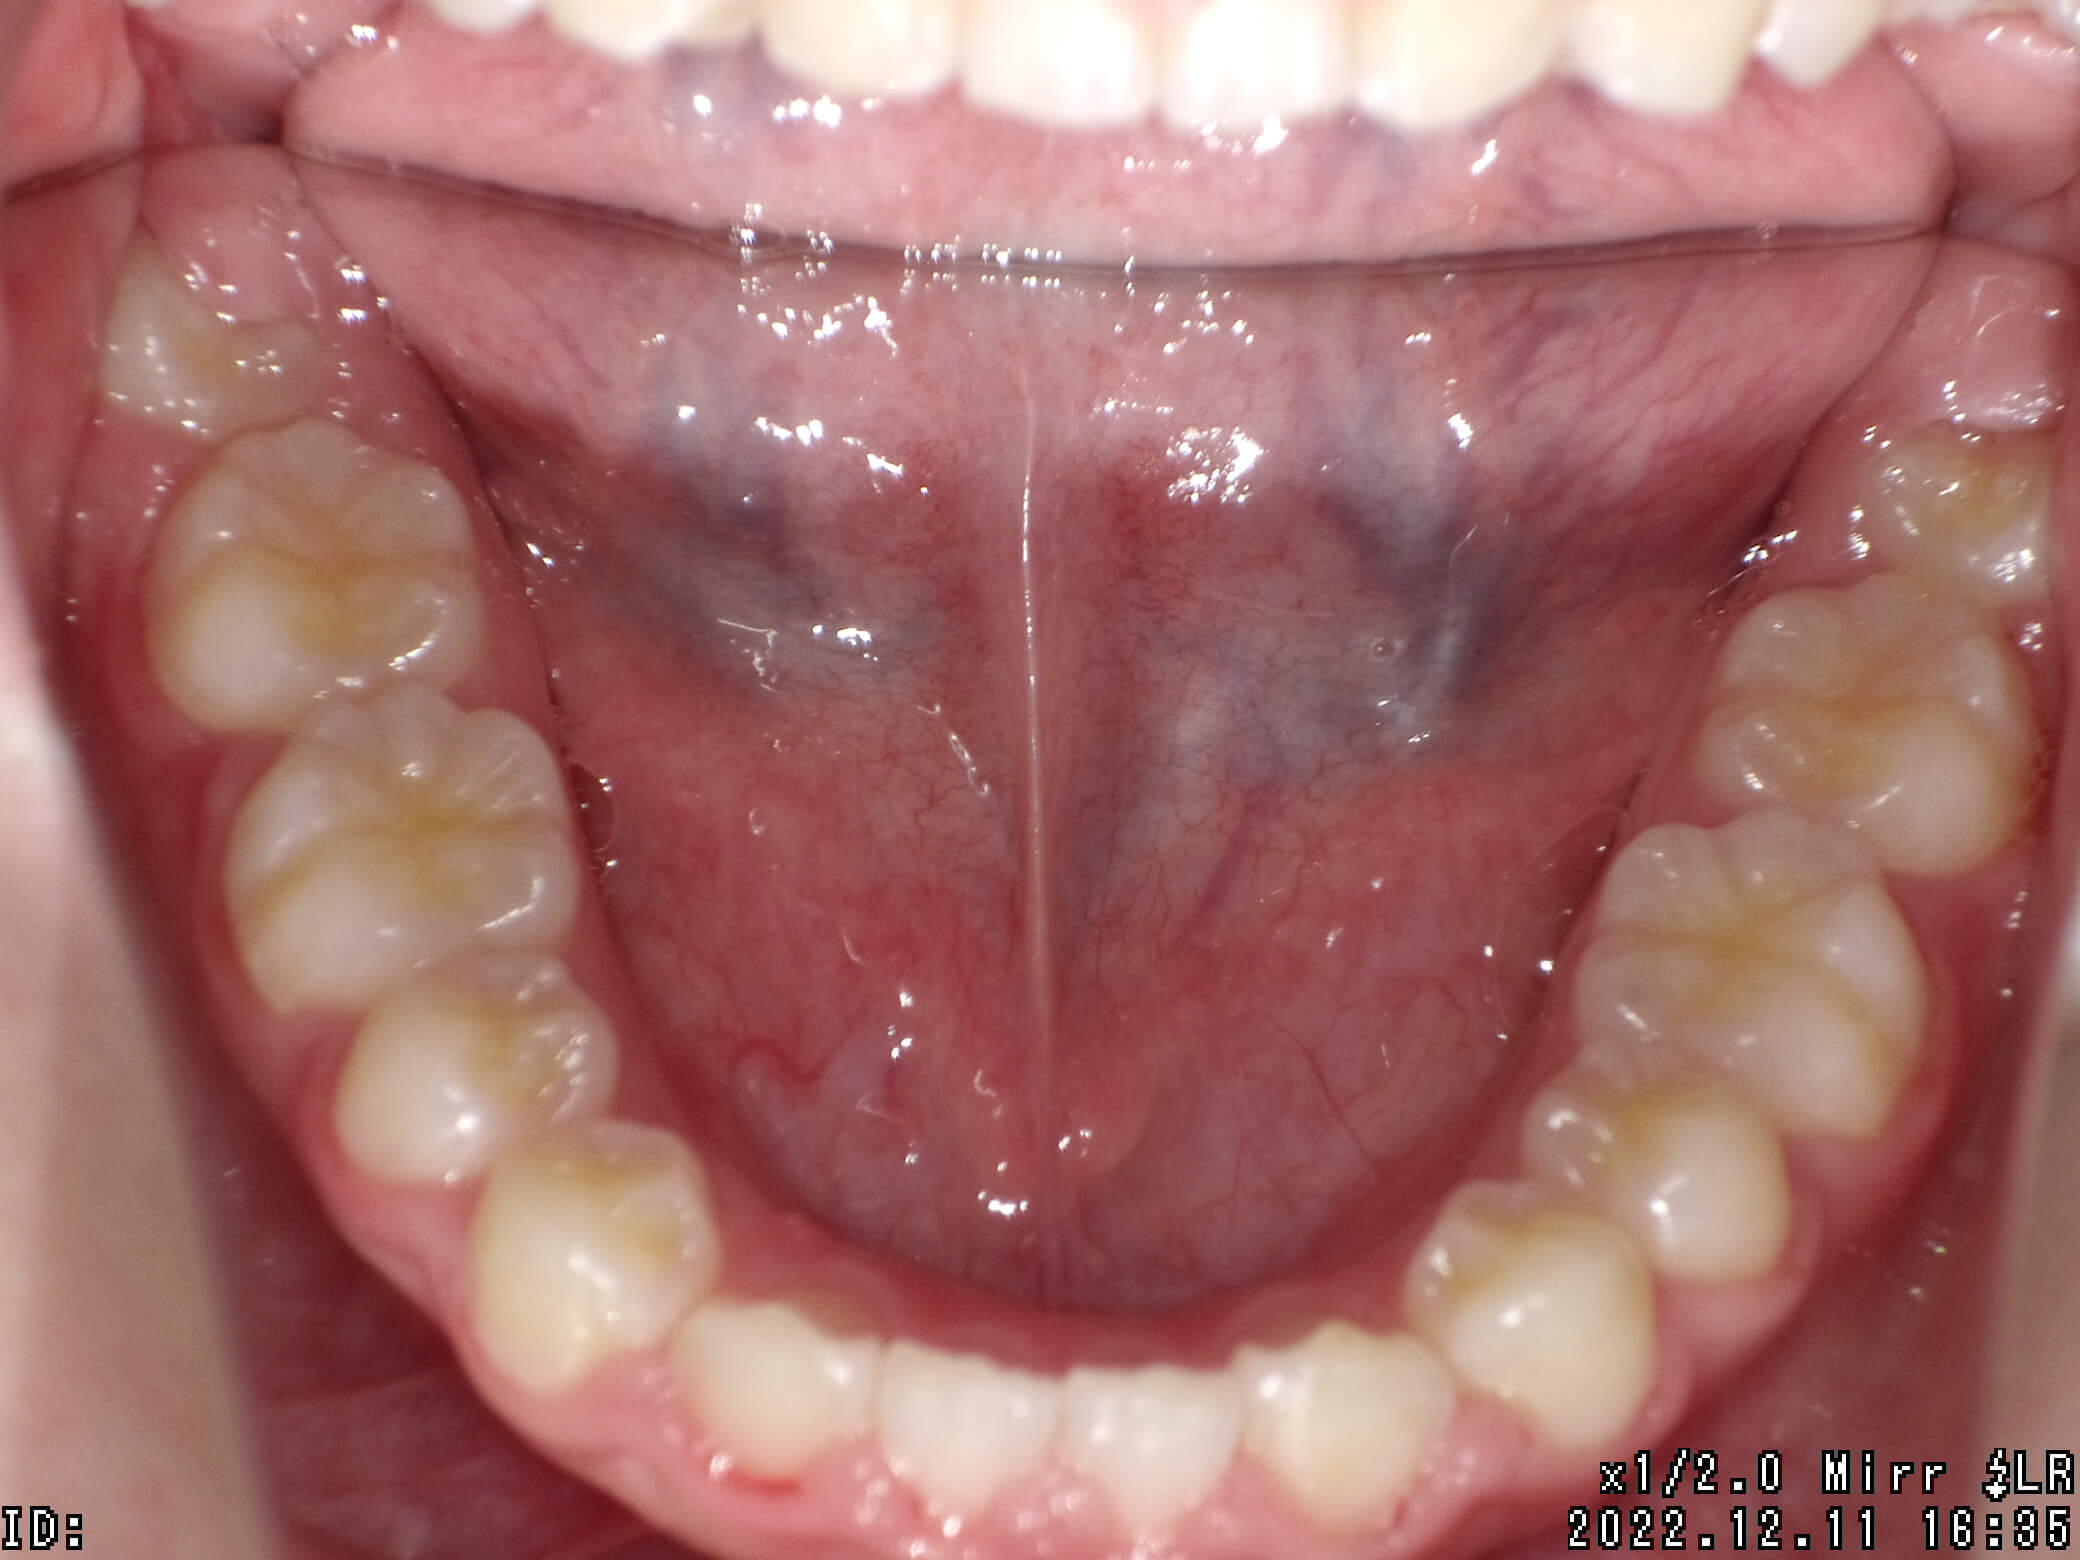

| 治療期間 | 2021年6月13日 〜2022年12月11日 |

|---|---|

| 治療費用 | 約770,000円 |

| 抜歯有無 | 抜歯あり |

| 矯正箇所 | クリアブラケット矯正 |